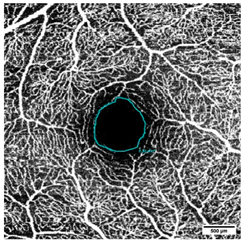

OCTA was acquired at an angle of 10° × 10° with lateral resolution of 5.85 µm/pixel, resulting in a retinal section of 2.9 × 2.9 mm (total scan size 8.41 mm2) (Figure 2). To ensure the correct image interpretation, the quality of the segmentation in horizontal foveal B-scan OCT and en face OCTA maps and in OCTA B-scans was verified by two experienced examiners.

Figure 2.

OCTA images of (a) Superficial Vascular Plexus (SVP), (b) intermediate capillary plexus (ICP), and (c) Deep Capillary Plexus (DCP) surrounding the macula. In the middle of the picture is the foveal avascular zone. Illustrations were created with the Heidelberg Eye Explorer.

The VAD was measured in three circles around the macula (c1, c2, c3, and in full: c1 + c2 + c3) (Figure 3 and Figure 4); the radius of the first circle amounts 0.4 mm. The second circle (c2) radius measures 0.75 mm and the third one (c3) 1.1 mm. Each of these circles was subdivided into 12 smaller areas. For each of these areas, the mean VAD was analyzed using the EAT and calculated in percentage (%).

Measurement of the foveal avascular zone (FAZ) in (a) Superficial Vascular Plexus (SVP), (b) intermediate capillary plexus (ICP), and (c) Deep Capillary Plexus (DCP).

The FAZ was manually measured in full thickness scans by two different examiners and the mean value of the measurements was noted for statistical evaluation (Figure 4). The total size of the FAZ area (mm2) was analyzed and recorded separately for each layer (SVP, ICP, and DCP) of the macula.